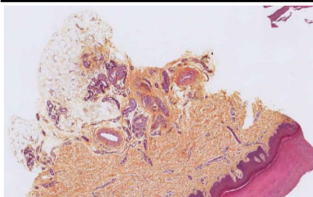

Decrit l’épithelium de la lAme de peau acrale

epithelium stratifié pavimenteux malpighien keratinisé